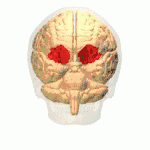

Орбитофронтальная кора

Орбитофронтальная кора (ОФК) — участок префронтальной коры в лобных долях головного мозга, принимающий участие в принятии решений. У человекообразных обезьян ОФК представлена совокупностью полей Бродмана под номерами 11, 12 и 13; у людей эта кора представлена полями 10, 11 и 47[1].

Орбитофронтальная кора анатомически синонимична вентромедиальной префронтальной коре. ОФК выделяется отдельно, поскольку содержит определенные нейронные связи, а также выполняет строго определенные функции. Принято считать, что ОФК является частью префронтальной коры, которая получает сигналы от магноклеточных нейронов, медиальных ядер таламуса, и принимает участие в представлении эмоций и поощрений во время принятия решений[2]. Название ОФК получила из-за своего расположения в области лобных долей, находящейся выше глазниц (орбит).